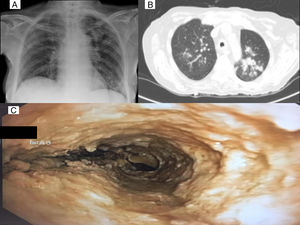

El micofenolato fue suspendido al mes del TPH por persistencia de enfermedad residual. El descenso de la inmunosupresión supuso la aparición de enfermedad de injerto contra huésped, que precisó tratamiento con metilprednisolona a dosis altas (2mg/kg/día). Durante el descenso de dosis, presenta cuadro de infección respiratoria con infiltrado radiológico en el lóbulo superior izquierdo (LSI). Se solicita broncoscopia, siendo la imagen endobronquial altamente sugestiva de traqueobronquitis aspergilar pseudomembranosa (fig. 1). Este caso se trata de una infección de brecha, seguramente favorecida por la corticoterapia1. La paciente recibió tratamiento con anfotericina B intravenosa y voriconazol, pero con mala evolución, falleciendo pocos días después2.